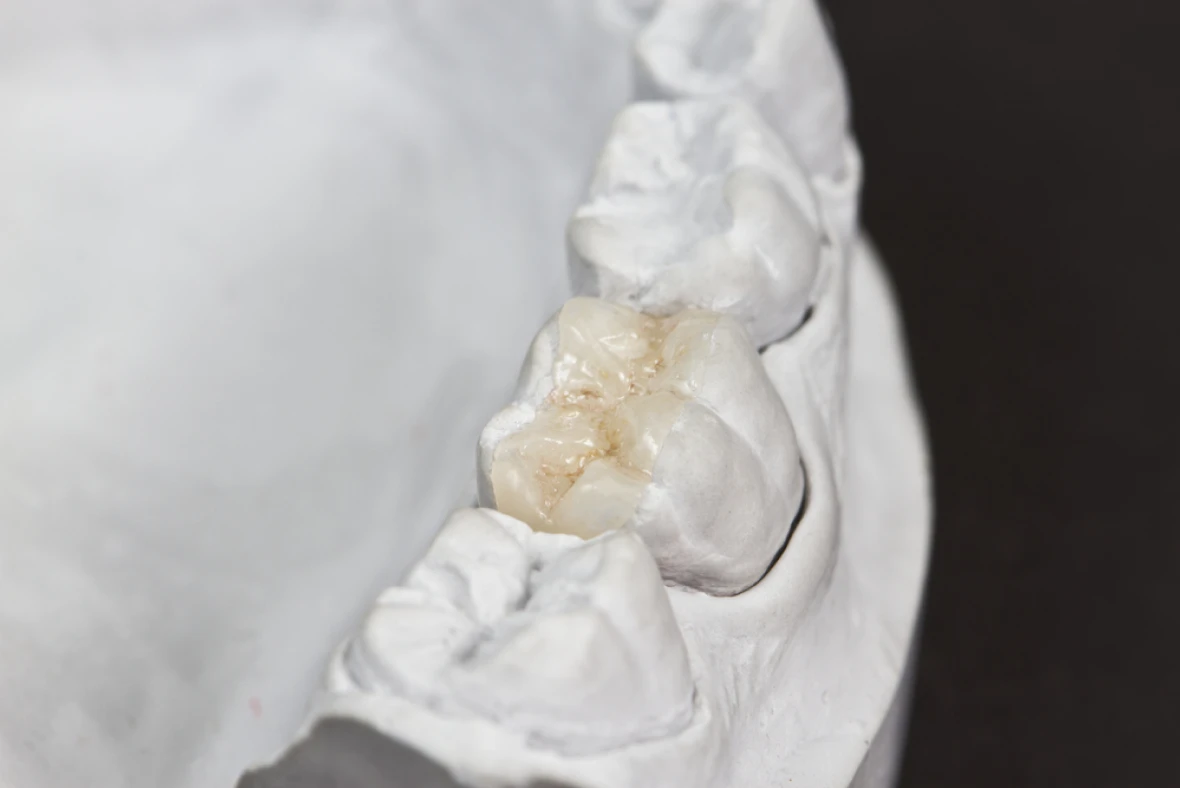

セラミックインレー

ハイブリッドインレー

セラミックインレーは陶材を材質としたつめものです。 ハイブリッドインレーは、セラミックとプラスチック性の材質を混ぜ合わせたつめものです。どちらも審美性に優れたつめものです。これに関しても、当院では耐久性に強く美しいe-maxセラミックも選択できます。